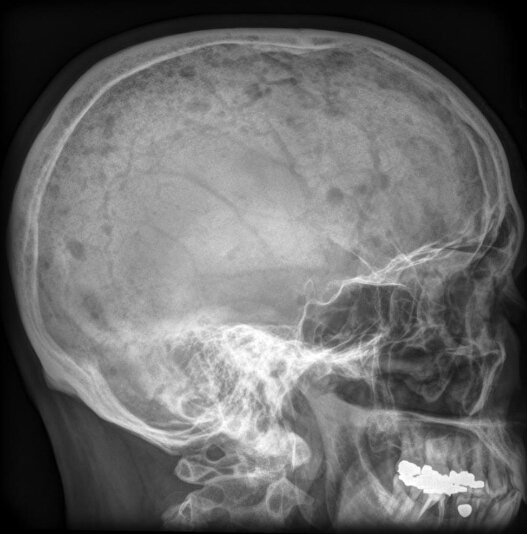

What is the diagnosis?

Multiple lytic calvarial lesions associated with mutiple myeloma

punched out lesions